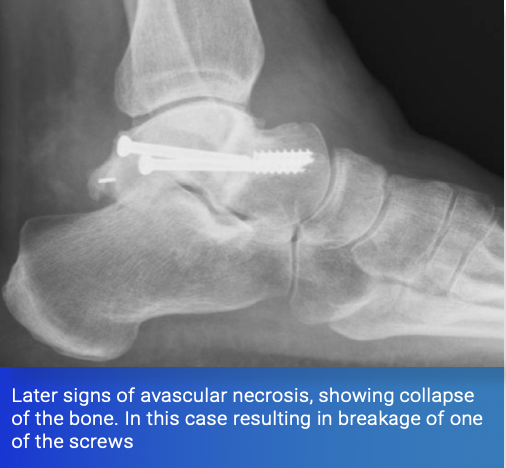

Certain fractures are renowned for damaging the blood supply of the bone. Common examples are fractures of the hip and fractures of the talus, the main bone in the ankle joint.

Talar neck fractures, if caused by a high-energy injury with significant displacement, can completely disrupt the blood supply to the body of the talus. This can cause the bone to die and collapse, resulting in arthritis and may necessitate salvage procedures such as fusions around the hindfoot.